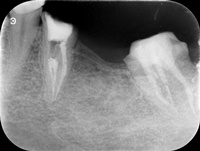

Pacjentka zgłosiła się z bólem. Ząb prawa dolna czwórka po leczeniu kanałowym. Nawracające dolegliwości bólowe, od kilku lat okresowo zaostrzające się. Podjęto decyzję o rewizji leczenia kanałowego. Udróżniono kanał korzeniowy, oraz odnaleziono kanał dodatkowy. Zdjęcie początkowe i zdjęcie po leczeniu endodontycznym pod mikroskopem.